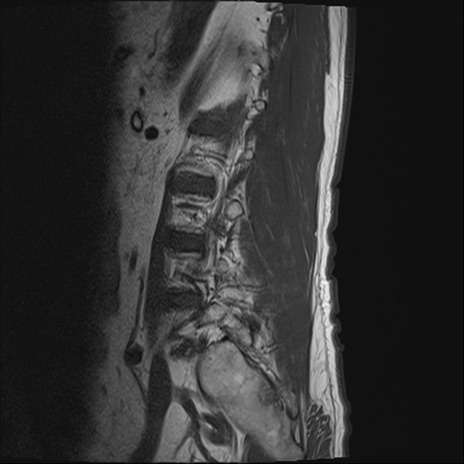

【症例】70歳代男性

【主訴】左下肢痛

【現病歴】2週間前くらいから腰痛、左下肢痛あり。左臀部から大腿、下腿外側のしびれが常時ある。歩行とともに同部位の痛みあり。

【身体所見】Lasegue70-/60+、Bragard-/±、PTR ±/±、ATR -/-、IP 5/5、TA 5/4、TS 5/5、EHL 右第1足趾なし/3、FHL 5/5、hypersthesia(-)、足背動脈触知良好

異常所見と診断は?